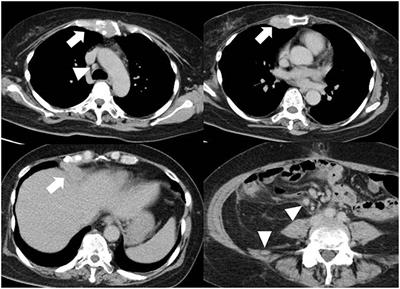

Endovascular Therapy for Concurrent Cardio-Cerebral Infarction in a Patient With Trousseau Syndrome